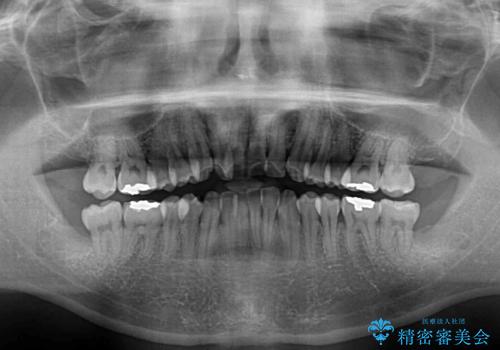

下顎骨が顕著に右側にずれている インビザラインによる咬合改善

下顎骨が顕著な左右差を持って成長したため、右側にずれている状態でした。

この方は元々骨格的な偏位が大きかったためか、治療中に下顎骨が上顎骨よりも右外側に誘導されて、右側の奥歯が全く咬合しない状態が続いてしまいました。